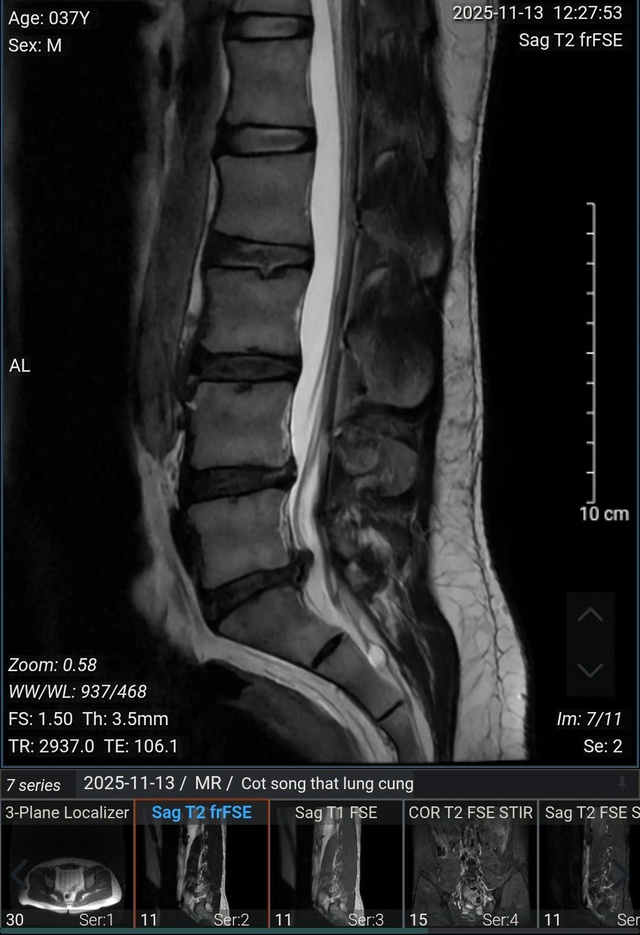

(Ảnh chụp MRI của anh Nam, 37 tuổi (Hà Nội)).

Kết quả chụp MRI cho thấy, bệnh nhân bị thoái hóa cột sống thắt lưng, thoát vị nội xốp các đĩa đệm từ L2/3 đến L5/S1, phình - thoát vị đĩa đệm L4/5 ra sau thể trung tâm gây chèn ép bao màng cứng, gây hẹp nhẹ ống sống, không gây chèn ép rõ rệt các rễ thần kinh; phình - thoát vị đĩa đệm L5/S1 ra sau thể trung tâm lệch trái gây chèn ép bao màng cứng, gây hẹp ống sống, hẹp ngách bên - lỗ tiếp và chèn ép các rễ thần kinh 1 bên ngang mức (trái > phải).